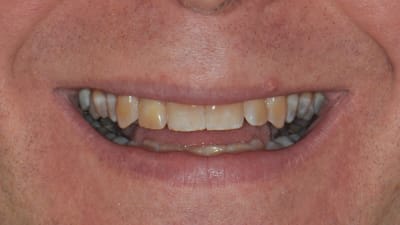

Continuing Education Implants The “All-on-4” Concept for Implant Rehabilitation of an Edentulous Jaw By Christopher CK Ho, BDS, Sascha A. Jovanovic, DDS April 01, 2014